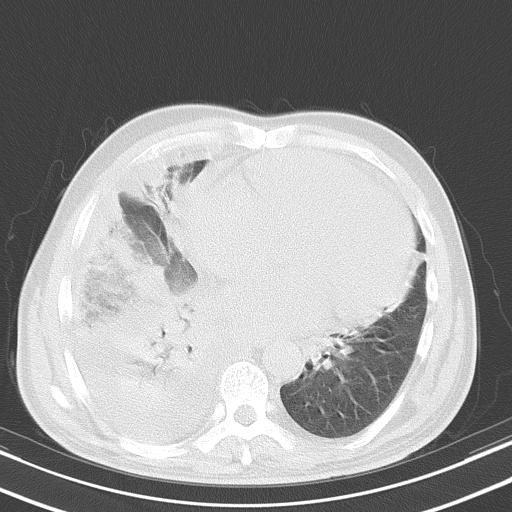

以下是引用zjzjr在2010-3-21 17:39:00的发言:[br]右下中心型肺癌并阻塞性肺炎/不张,纵膈淋巴结肿大,右侧大量胸腔积液,左侧少量胸腔积液

以下是引用zxl51642在2010-3-21 17:06:00的发言:[br]右下中心型肺癌并阻塞性肺炎/不张,纵膈淋巴结肿大,右侧大量胸腔积液,左侧少量胸腔积液,少量腹水。建议纤维支气管镜进一步检查。